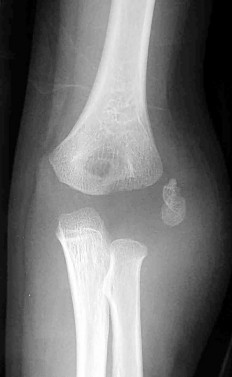

A 4-year-old child sustains a mildly displaced (<2mm) lateral condyle fracture of the humerus, which is treated non-operatively in a long arm cast. Three months later, radiographs reveal a frank nonunion of the lateral condyle. If left untreated, what late neurological complication is most characteristic of this condition?

Explanation